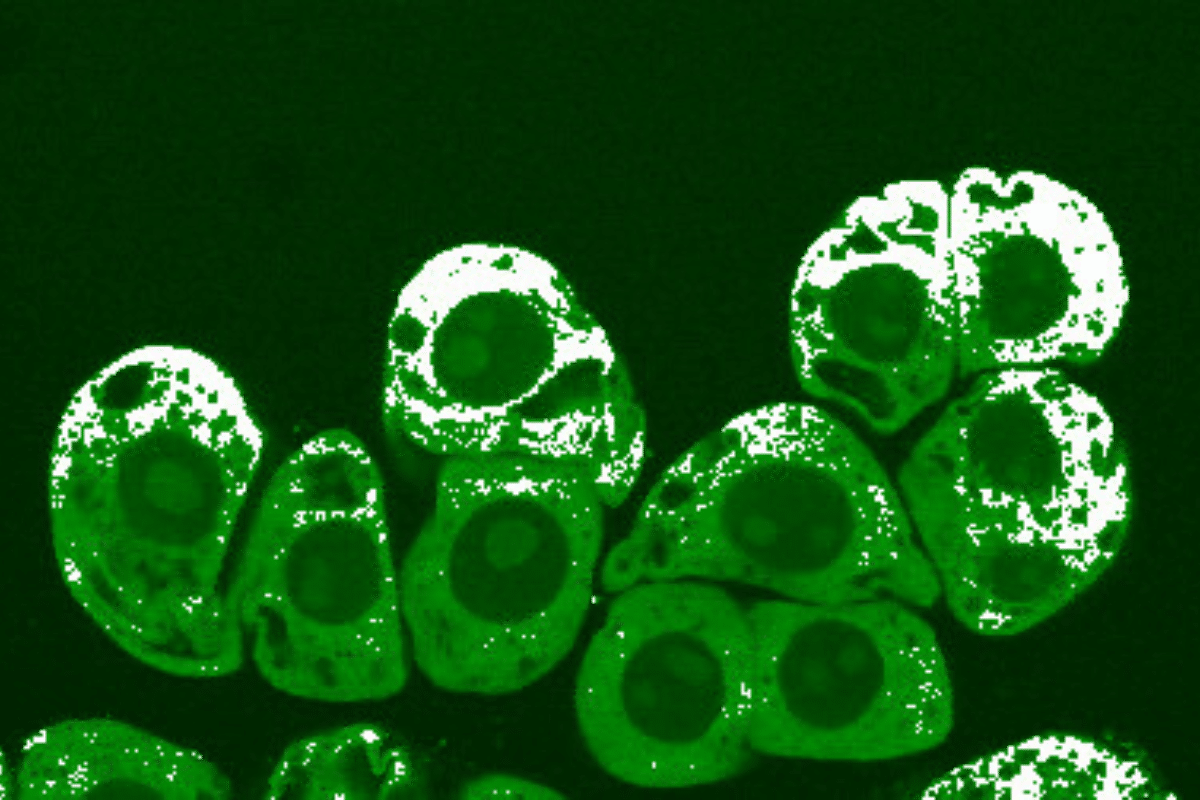

Skin

The late 90s was a big moment for nitric oxide because in 1996, two years before Murad, the Nobel Prize, and Viagra, dermatologist Richard Weller described how our skin, the largest organ of the human body, is apparently a massive repository of the stuff, although in forms that are chemically bound up and unusable. But similar to the mouthwash situation, he theorized that the nitric oxide found on skin is generated through the activity of hosted microbes interacting with our sweat.